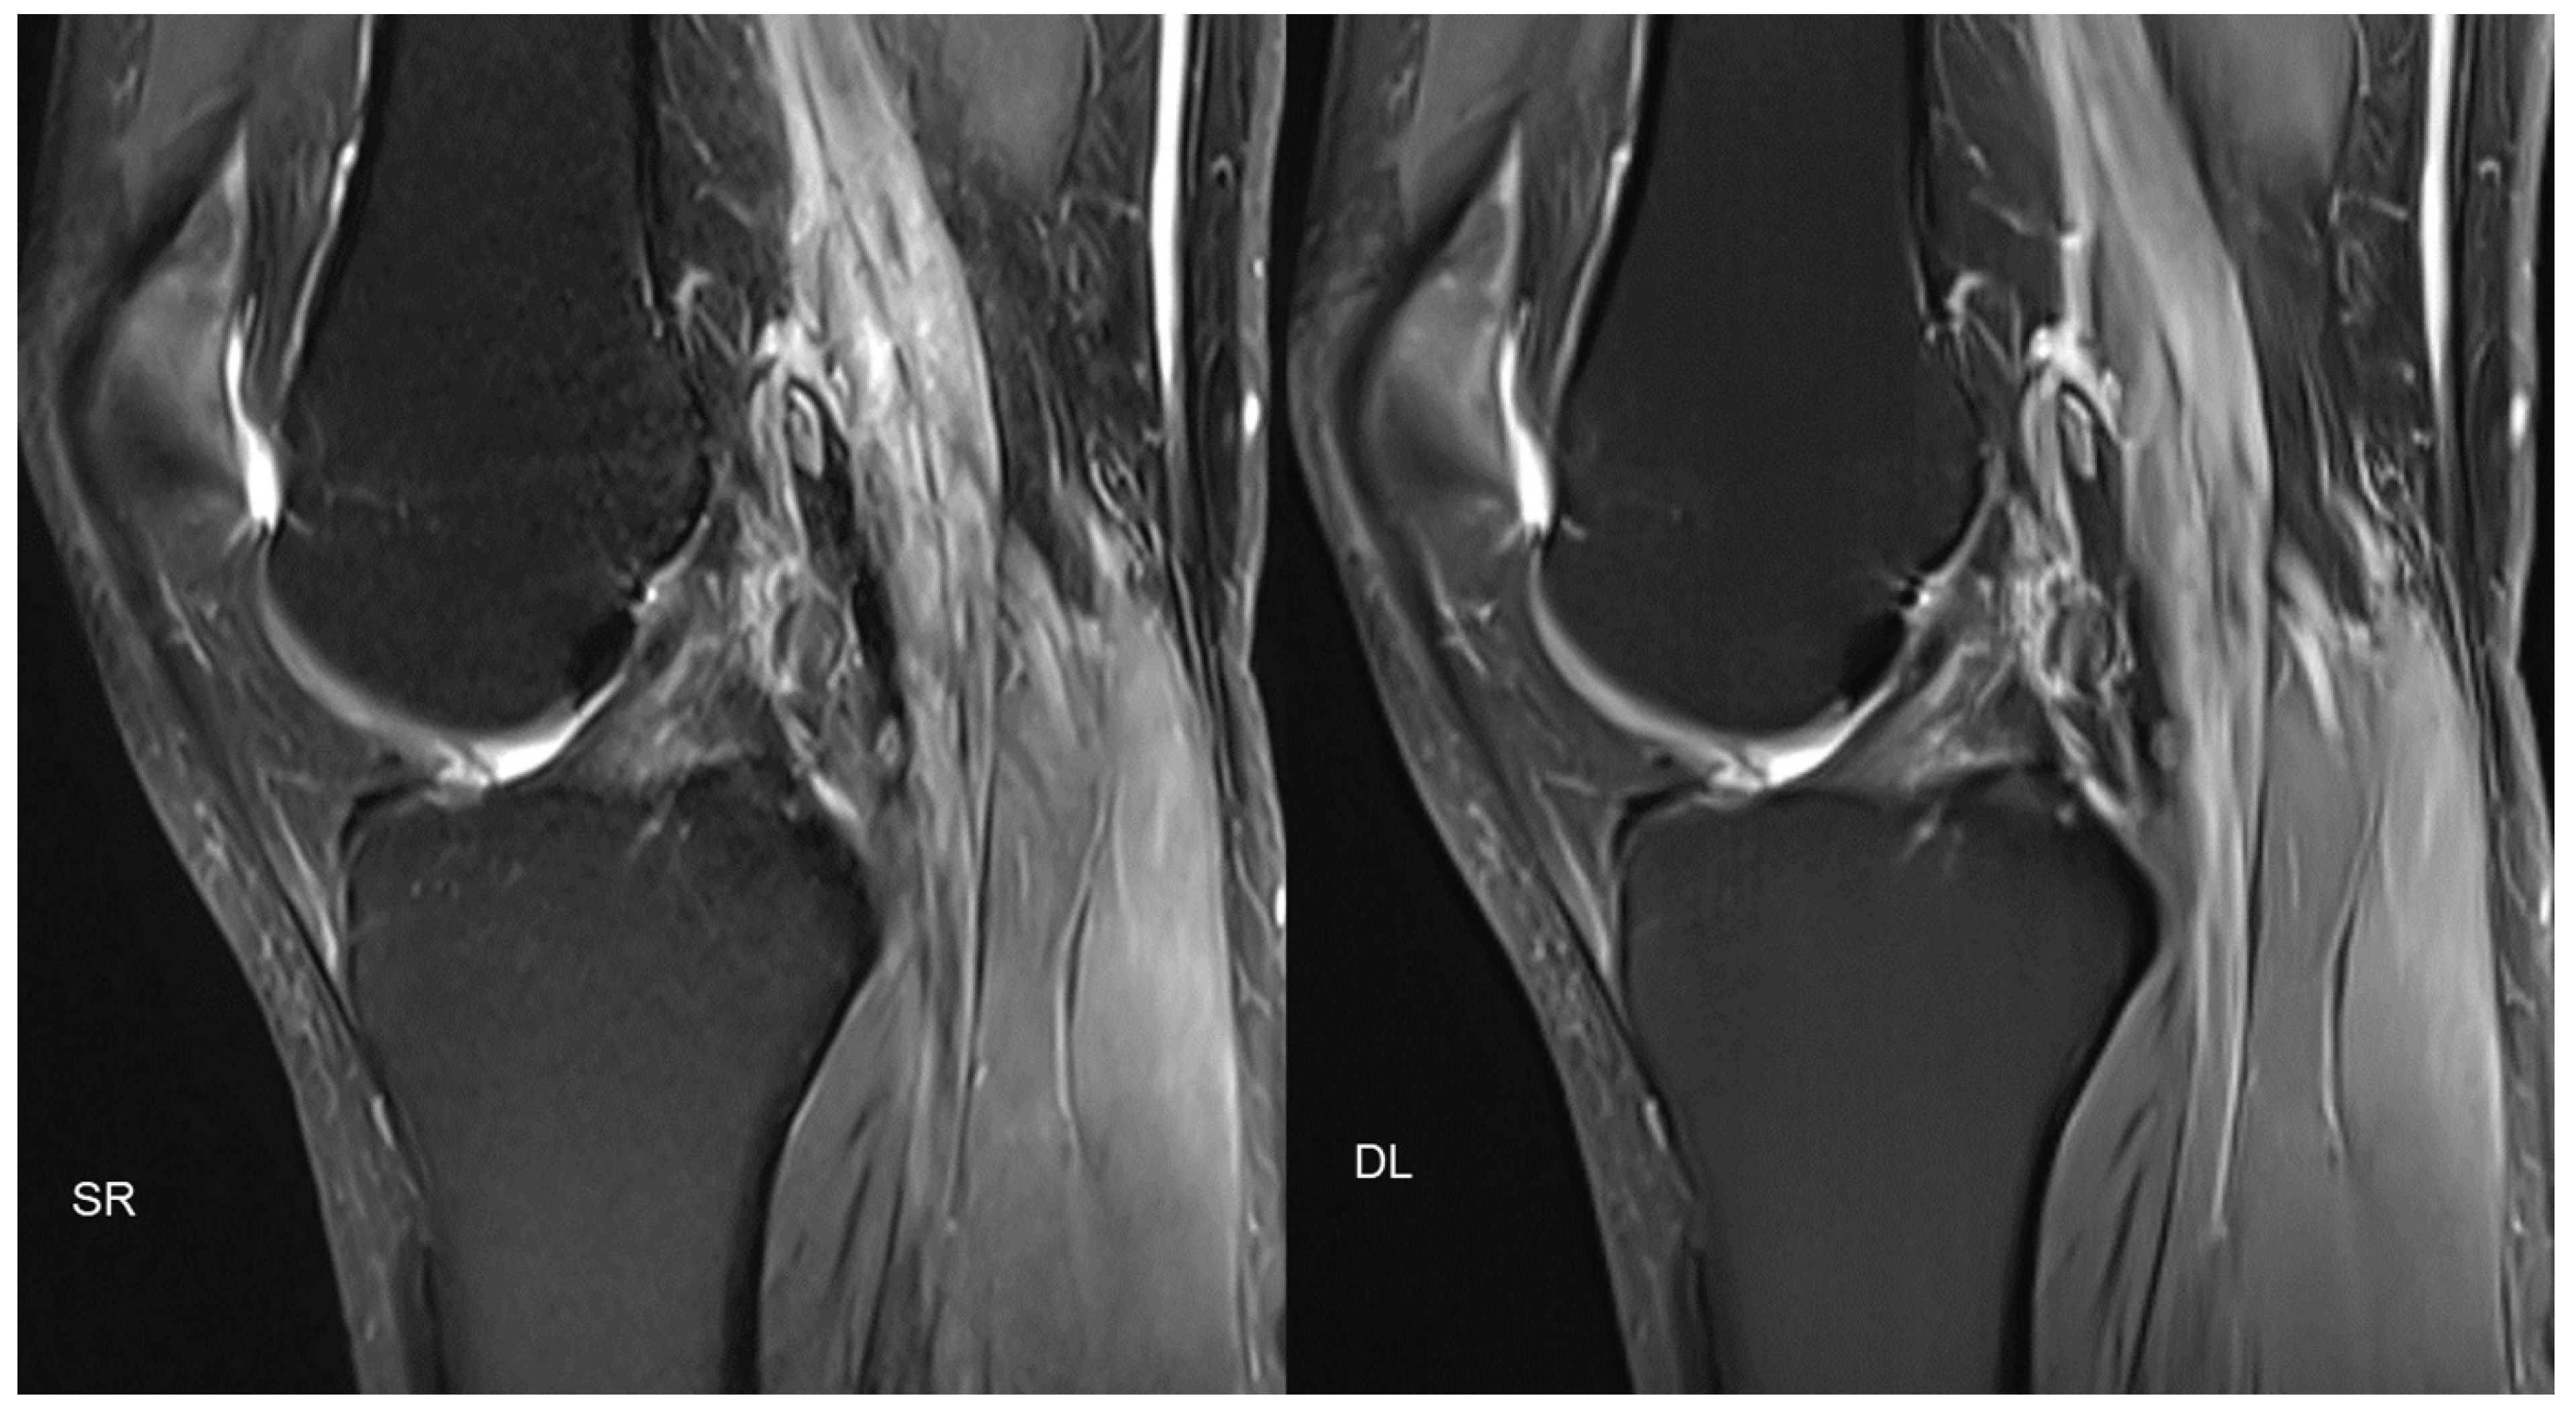

- Recht, M.P.; Zbontar, J.; Sodickson, D.K.; Knoll, F.; Yakubova, N.; Sriram, A.; Murrell, T.; Defazio, A.; Rabbat, M.; Rybak, L.; et al. Using Deep Learning to Accelerate Knee MRI at 3 T: Results of an Interchangeability Study. Am. J. Roentgenol. 2020, 215, 1421–1429. [Google Scholar] [CrossRef]